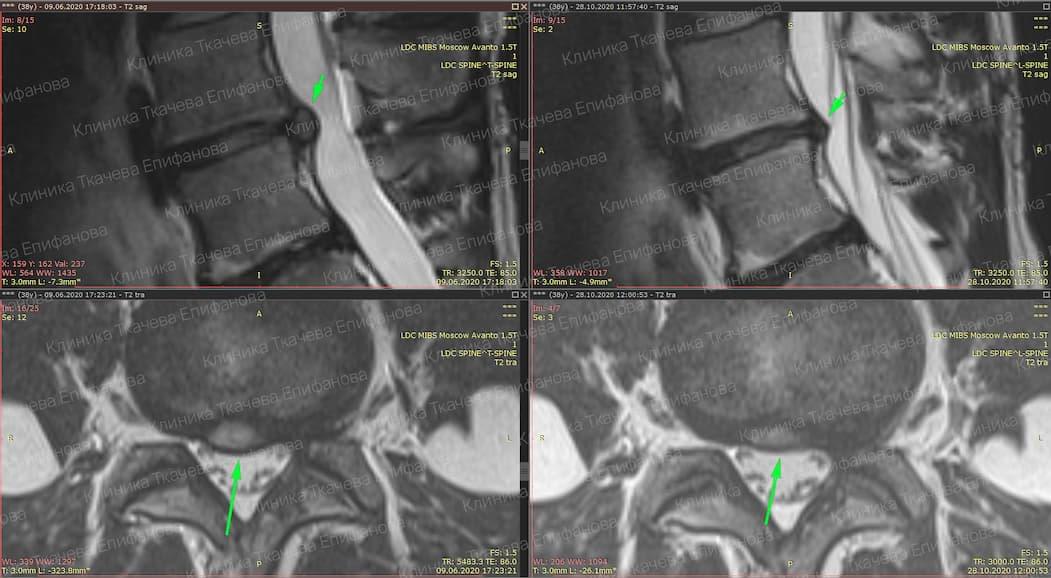

* Резорбция — процесс уменьшения грыжи диска за счет естественных физиологических способностей организма. Это основа эффективного лечения грыжи и альтернатива операции.

Метод модулируемой резорбции позволяет ускорить этот процесс, взять боль под контроль и улучшить качество жизни.